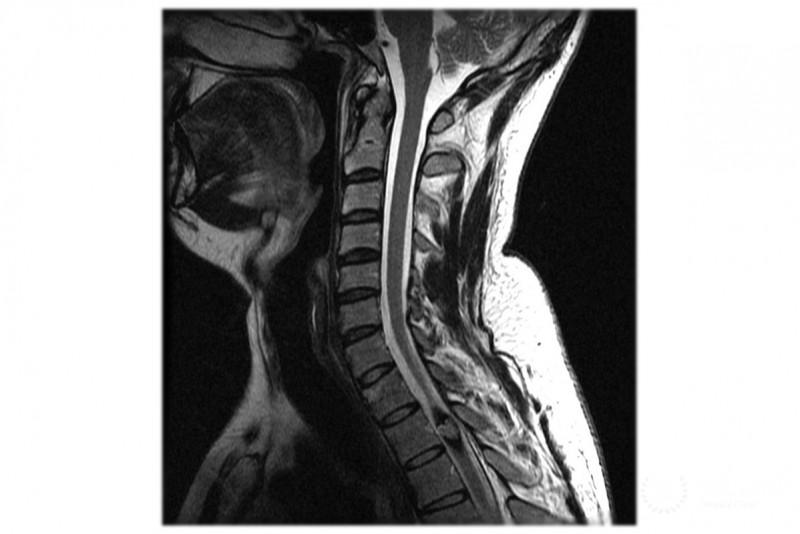

- МРТ;